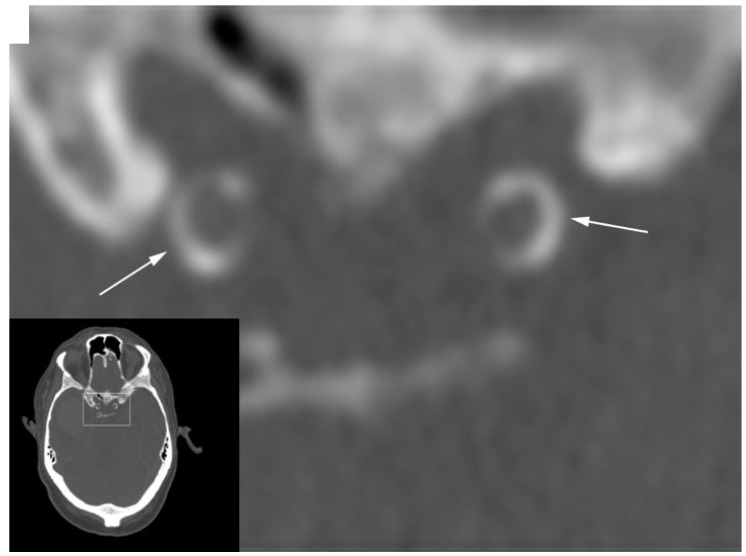

A healthy vasculature with well-regulated perfusion and pulsatility is essential for the brain. One vascular structure that has received little attention is the carotid siphon. The proximal portion of the siphon is stiff due to the narrow location in the skull base, whilst the distal portion is highly flexible. This flexible part in combination with the specific curves lead to lower pulsatility at the cost of energy deposition in the arterial wall. This deposited energy contributes to damage and calcification. Severe siphon calcification stiffens the distal part of the siphon, leading to less damping of the pulsatility. Increased blood flow pulsatility is a possible cause of stroke and cognitive disorders. In this review, based on comprehensive multimodality imaging, we first describe the anatomy and physiology of the carotid siphon. Subsequently, we review the in vivo imaging data, which indeed suggest that the siphon attenuates pulsatility. Finally, the data as available in the literature are shown to provide convincing evidence that severe siphon calcifications and the calcification pattern are linked to incident stroke and dementia. Interventional studies are required to test whether this association is causal and how an assessment of pulsatility and the siphon calcification pattern can improve personalized medicine, working to prevent and treat brain disease.